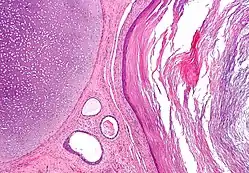

![]() صورة مجهرية لورم مسخي يظهر نسيجا يحتوي على طبقات التبرعم الثلاث: الأديم المتوسط (غضروف غير ناضج - الزاوية العليا اليسرى من الصورة)، الأديم الباطن (غدد هضمية - أسفل وسط الصورة) والأديم الظاهر (البشرة - يمين الصورة). صورة مجهرية لورم مسخي يظهر نسيجا يحتوي على طبقات التبرعم الثلاث: الأديم المتوسط (غضروف غير ناضج - الزاوية العليا اليسرى من الصورة)، الأديم الباطن (غدد هضمية - أسفل وسط الصورة) والأديم الظاهر (البشرة - يمين الصورة). | |